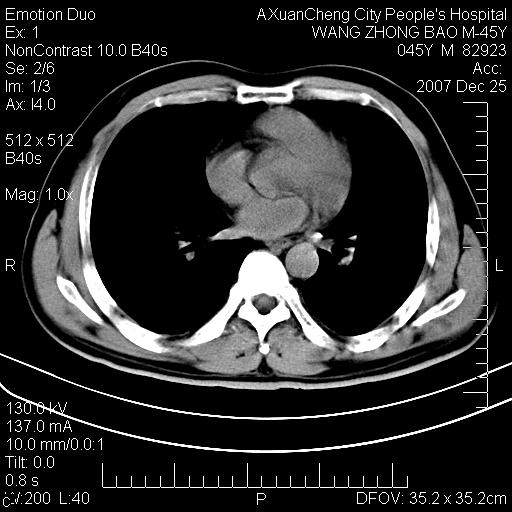

以下是引用qiuleiyu在2007-12-25 18:14:00的发言:[br]胰腺增大,周边渗出改变,肾前筋膜明显增厚,示少量积液.胆囊壁毛糙,周边少许渗出,胆总管壁厚,异常强化,然扩张不明显.结合病程急短;考虑;胆管炎,胆囊炎,胆源性胰腺炎可能大,请结合实验室检查及随访.

以下是引用lisihao在2007-12-25 14:23:00的发言:[br]急性水肿型胰腺炎[br]依据:1、胰腺弥漫性肿大,边缘稍毛糙;[br] 2、双侧肾周筋膜增厚,尤以左侧为甚(重要征象)[br] 3、双侧后胸膜增厚(刺激性炎症);[br] 4、结合病史,查血尿淀粉酶应该可以确诊。